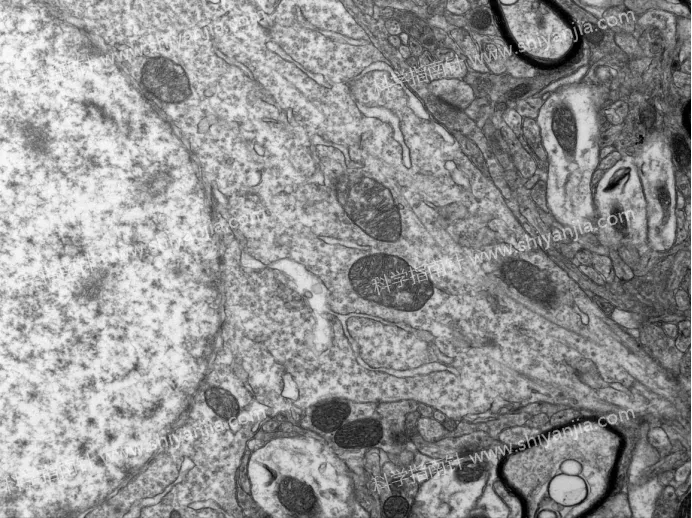

1.灌流处理是结构保存的基础:灌流组样本因固定液快速渗透组织,有效终止了酶促反应,样本结构保存效果远优于不灌流组;不灌流组即使 0 分钟快速取材,神经元也会出现早期自溶迹象。

灌流组

2.2 分钟是黄金取材窗口:灌流组 2 分钟内取材,样本超微结构无显著退化,膜结构清晰、细胞器形态完好,是兼顾操作可行性与样本质量的最佳时间。

灌流组